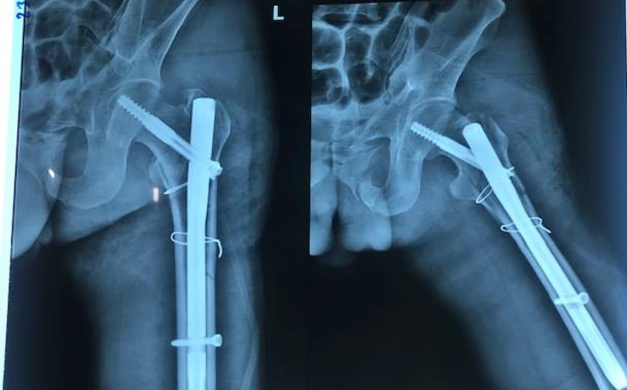

Anh Hiền ngã từ độ cao 8m xuống đất khi thi công một công trình ở TP.HCM, chấn thương nặng.